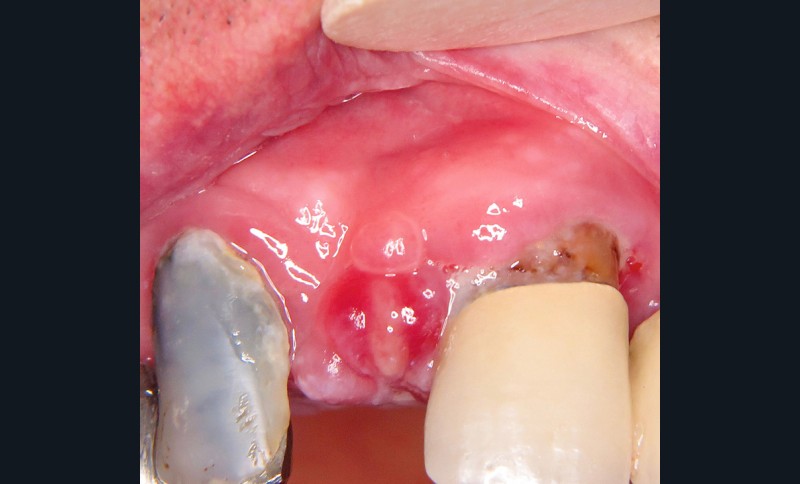

4. Épulis postextractionnel

- Granulome intra-alvéolaire à la suite d’une avulsion dentaire (fig. 4a et b).

- Absence de cicatrisation spontanée.